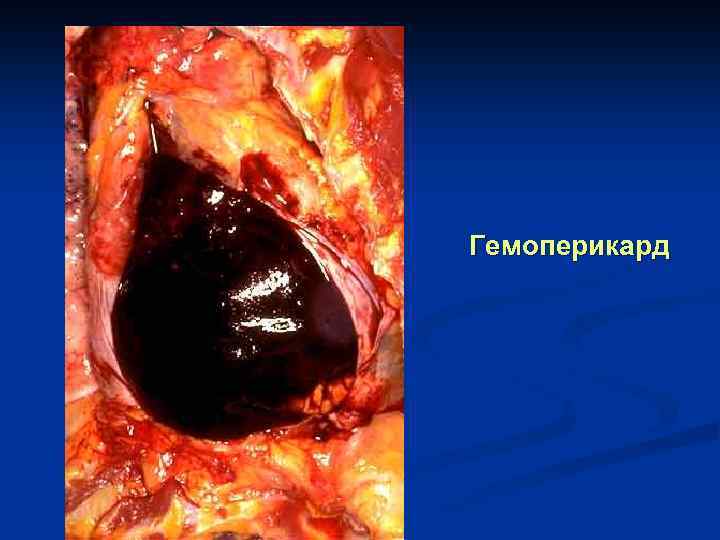

Гемоперикард

Тампонада сердца